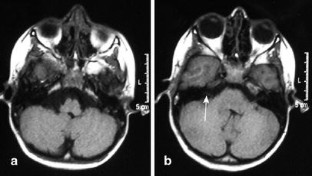

Facial nerve palsy in posterior fossa arachnoid cysts: report of two cases

Two patients with a posterior fossa arachnoid cyst responsible for isolated facial nerve palsy are reported.

The relationships between the cyst and the facial nerve and between the facial nerve palsy and the size variation of the cyst are discussed and documented by pre- and postoperative magnetic resonance imaging.

Fig. 3